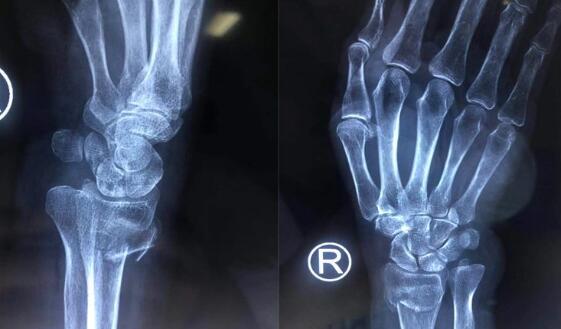

(图为术前检查)

经过检查发现,老太太的右桡骨远端粉碎性骨折,骨折移位严重。手外二病区的熊祖国医师告诉王老太的家属,高龄老年患者骨质疏松,骨折愈合缓慢,选择夹板固定的保守治疗非常容易导致骨折再次移位;同时夹板固定时间长,严重影响右手、右腕功能,导致关节僵硬、活动受限,还可能会引起一些并发症,降低生活的质量。而且王老太骨折断端错位比较严重,石膏外固定已无法恢复。王老太及家人同意手术治疗。